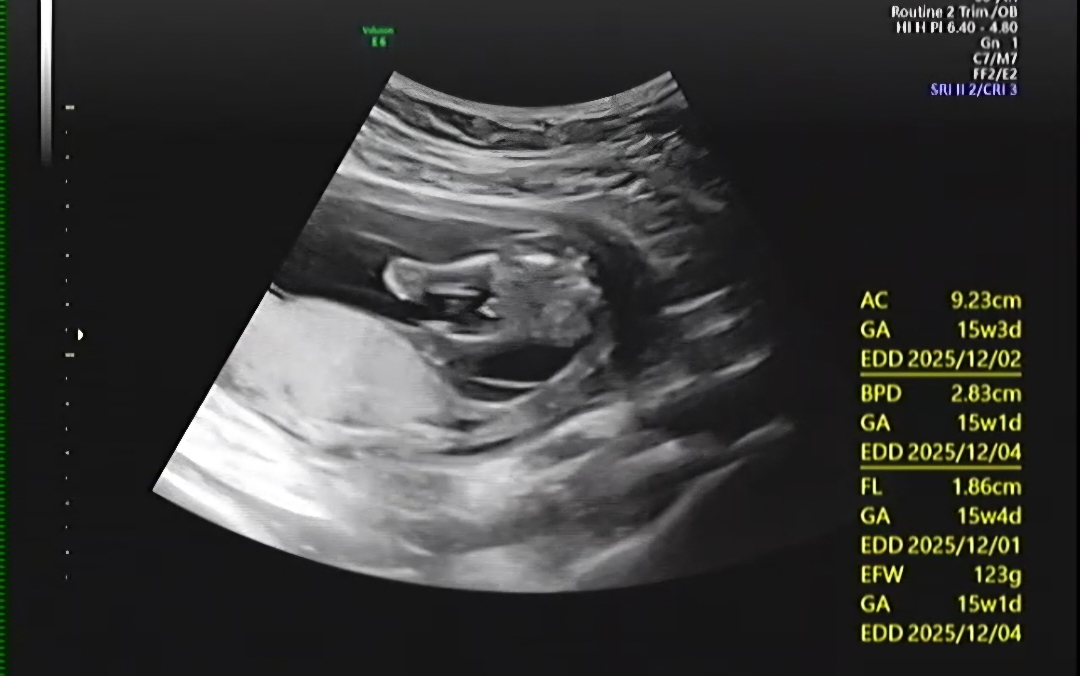

15주차 확실할까요?

저게 고추일까요? 삼각점일수있을까요? 나중에 또 달라질수있을까요?

15주차아면.. 아들 맞는 것 같습니당

아들같아유~~!!

삼각점처럼 보이네요!!